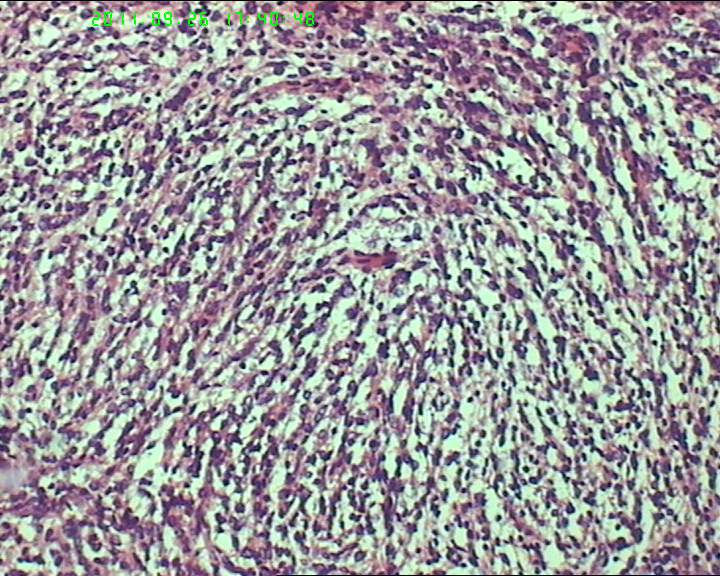

鉴别诊断排排队:1、GIST,2、MPNST,3、去分化脂肪肉瘤,4、恶性间皮瘤,5、恶性SFT,6、平肉

主要考虑前二者。CD34,CD117,S-100,BCL-2,SMA, D2-40,CR, VIM. 结果如何?请楼主揭谜底吧。